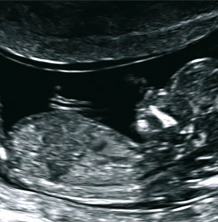

Differenzierte Ultraschalluntersuchung der Stufe DEGUM II zur weiterführenden Diagnostik und Ausschluß von Fehlbildungen, Entwicklungsstörungen und anderen Gefahrenzuständen für das ungeborene Kind. Idealer Untersuchungszeitpunkt ist der Zeitraum zwischen der 20. und 22. Schwangerschaftswoche. Bei speziellen Fragestellungen ist die Untersuchung auch in anderen Wochen möglich. Bei dieser Untersuchung wird das Kind genau vermessen (Fetometrie), alle Organe des Feten , einschließlich Gehirn und Herz, beurteilt, sowie Plazenta- und Fruchtwasserverhältnisse überprüft. Damit können bis zu 95% der schweren Fehlbildungen und Entwicklungsstörungen erkannt und ggf. behandelt werden.

Die Möglichkeit, Ultraschallaufnahmen dreidimensional zu speichern, wird als 3D Technik bezeichnet. Dank sehr schneller Verrechnung dieser Bilder ist es möglich diese Bilder annähernd in Echtzeit wiederzugeben. Dann spricht man von 4D- Aufnahmen. Dieses Werkzeug nutzt der Pränataldiagnostiker, um Organe genauer untersuchen zu können (z. B. Gehirn). Wie bei einer Kernspinnuntersuchung können dreidimensionale Volumenblöcke gespeichert werden, die dann in der Nachschau beliebig gedreht und geschnitten werden können. In der Hand des Geübten ein großer diagnostischer Gewinn. Natürlich können auch Oberflächen (z.B. Gesicht) betrachtet werden, dies stellt jedoch nur einen kleinen Anteil an Möglichkeiten der 3D Technik dar.